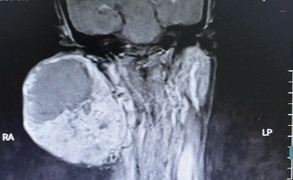

Mất thính lực kéo dài, người đàn ông đi khám phát hiện khối u hiếm nằm sâu nền sọ, sát động mạch cảnh trong, đe dọa tính mạng nếu không phẫu thuật.